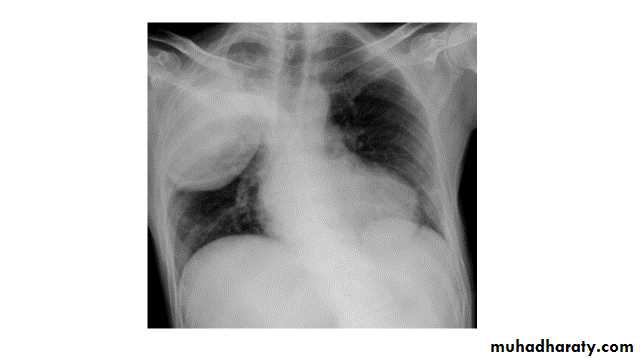

Right lower lobe consolidation

manifests as airspace shadowing that abuts the right hemidiaphragm,obliterating the crisp margin of the hemidiaphragm and normal aerated lung.

bulging fissure sign refers to lobar consolidation where the affected portion of the lung is expanded. It is now rarely seen due to the widespread use of antibiotics.